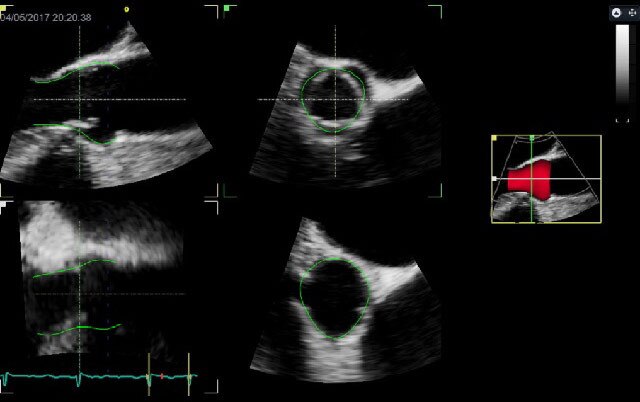

Auto EF 2.0**

4D Auto LAQ*